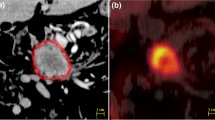

Contouring was performed using specialized software (RTx, Mirada Medical, Oxford UK). PET and CT images were displayed using preset window levels and/or colour scale per a standardized institutional protocol (Fig. 1). Patients were contoured per the National Cancer Research Institute (NCRI) UK NeoSCOPE trial protocol [18]. The tumour length and outlines were derived from the diagnostic imaging which included an Endoscopic Ultrasound, contrast-enhanced CT and 3D PET-CT. The longest tumour dimension was used for outlining. The maximal length of the tumour with specific reference to an anatomical structure e.g. carina or superior aortic arch was defined on all imaging techniques. This enabled the oncologist and radiologist to identify the superior and inferior extent of the diseased oesophagus in relation to these structures; thereby allowing them to outline this segment of the entire circumference of oesophagus to be outlined. All the 4D CT and PET scans included at least one of the reference structures (e.g. superior aortic arch or carina) and therefore the target volumes were produced consistently on each of these datasets with reference to these structures [2]. Local nodal involvement was included in the target volume but more distant nodes were not. An experienced radiation oncologist contoured all target volumes with access to clinical details and standard-of-care imaging; PET-derived contours were generated by the same radiation oncologist contouring with an experienced dual-certified Nuclear Medicine Physician/Radiologist. GTVs were delineated on i) 10-phase planning 4D CT, ii) 10-phase 4D CT inherently co-registered to 3D PET-CT acquired at the same scan session and iii) 4D PET-CT. CTV was delineated and trimmed to anatomical boundaries (vertebrae, pericardium, pleura). 4D datasets from each series were used to generate an internal target volume (ITV) encompassing effects of physiological motion on the CTV. Expansion to PTV was the ITV of each series with a 5-mm margin in all directions. (Fig. 2). A minimum interval of 2 weeks was specified between delineation using each different methodology for each patient, to minimize any potential for intra-observer recall.